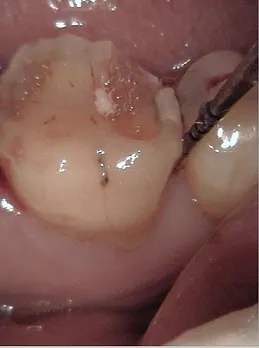

Tooth coloured and non-tooth coloured filling materials are available to suit both aesthetic and functional purposes. Generally, tooth coloured filling materials are preferred, from glass ionomer cement (fluoride releasing) to different types of composites.

In the case of some root canal treated teeth, posts may be required in certain circumstances, to stabilise the core of the tooth before a crown is applied. This is to improve the longevity of the crown. We also offer inlay and onlay restorations in porcelain or metal forms.